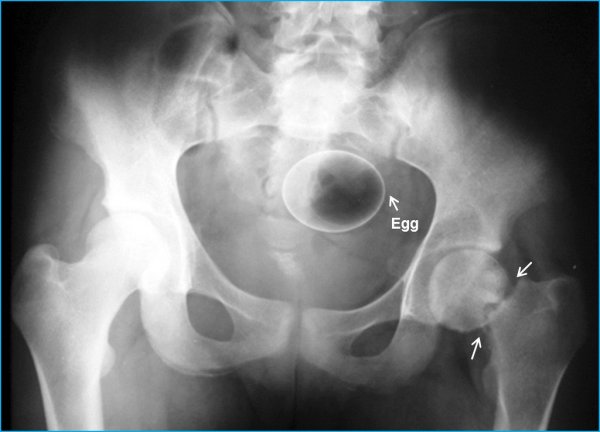

Специалисты по рентгеновской диагностике регулярно сталкиваются с посторонними предметами внутри тела человека. Обычно лишние предметы попадают в пищеварительную систему из-за неосторожности при еде или во время неудачных любовных игр. Почти всё удается вытащить — с хирургическим вмешательством или без него. выбрал самые необычные находки радиологов, которыми они делились на сайте Radiopaedia.org.